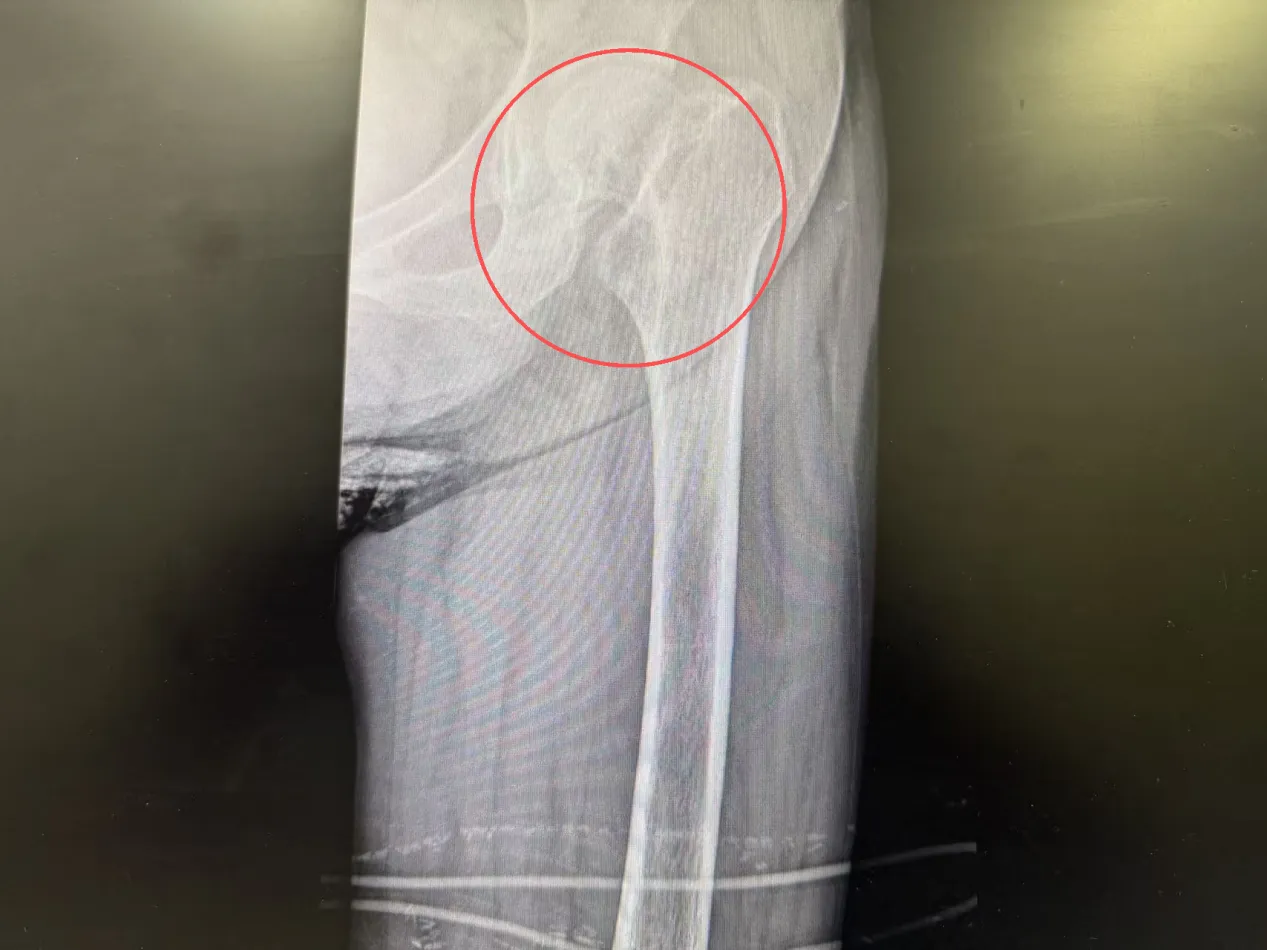

入院检查结果让医生们格外揪心,除了左侧股骨颈骨折,刘奶奶还患有重度骨质疏松、2型糖尿病、双侧多发肋骨骨折(右侧3-7肋、左侧5-7肋)、陈旧性脑梗死、脑萎缩、间质性肺炎及肺结节等多种基础疾病。更棘手的是,长期卧床加上糖尿病影响,她的血糖控制不佳,肺功能也较差,给后续治疗带来了很大的麻烦。

考虑到刘奶奶的复杂病情,骨科一病区团队迅速组织多学科会诊,邀请内分泌科医生介入,通过胰岛素泵精准调控血糖,还指导刘奶奶进行踝泵训练、股四头肌等长收缩等康复锻炼,为手术筑牢基础。待刘奶奶血糖平稳、身体状况达到手术条件后,由骨科一病区杨鹏主任主刀,为她顺利实施了关节置换手术。